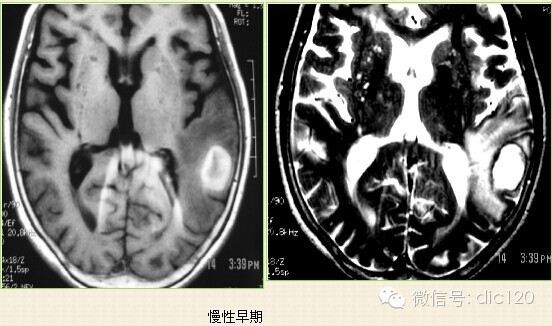

4.慢性期(2周后):水肿消失,正铁血红蛋白演变成含铁血黄素,血肿小可填充,大则遗留囊腔。